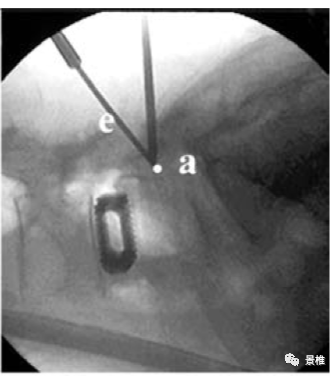

进针点位于棘突根部,指向对侧横突中点与椎弓根外缘交界处。

术中C臂透视正侧位所指向的关键点。